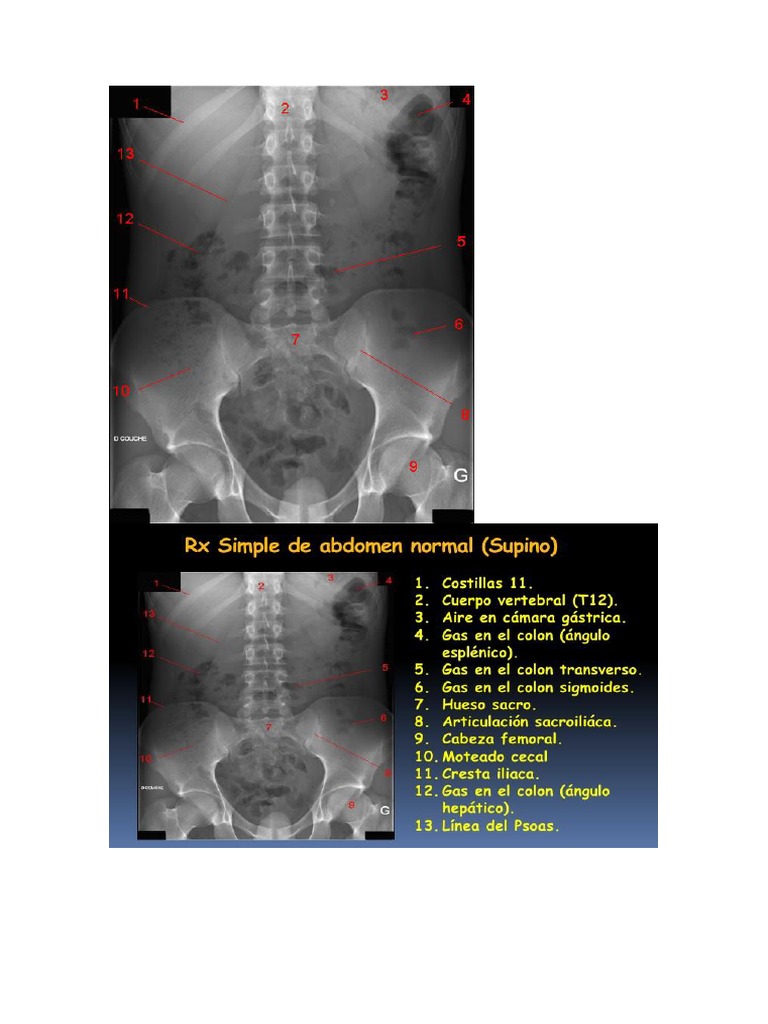

Rx simple de abdomen

Es importante tener en cuenta la división regional del abdomen, pues en cada zona se

localizan diferentes estructuras. A continuación se describirá cada una de estas regiones

y los

elementos que allí se proyectan:

Hipocondrio derecho

- Hígado: Área radiopaca, homogénea, en forma de semiluna, en su borde

superior relacionada con el hemidiafragma derecho y en su borde inferior

con la vesícula biliar. y el reborde costal anterior.

- Vesícula biliar: Localizada en la parte media del borde inferior del hígado.

- Bulbo duodenal: En relación con el hígado y la vesícula biliar.

- Riñón derecho – glándula suprarrenal: Se observan como formaciones

radiopacas.

Hipocondrio izquierdo

- Bazo: Es una formación radiopaca ubicada en la zona superior del

hipocondrio izquierdo.

- Riñón izquierdo: Se observa radiopaco con una orientación hacia fuera y

hacia abajo (siguiendo el borde externo del psoas) igual que en el riñón

derecho.

Epigastrio

- Estómago: En el que se observa una formación radiolúcida que corresponde

al gas de la cámara estomacal (burbuja gástrica).

Flanco derecho

- Ángulo hepático del colon.

- Colon ascendente.

Flanco izquierdo

- Ángulo esplénico del colon.

- Colon descendente.